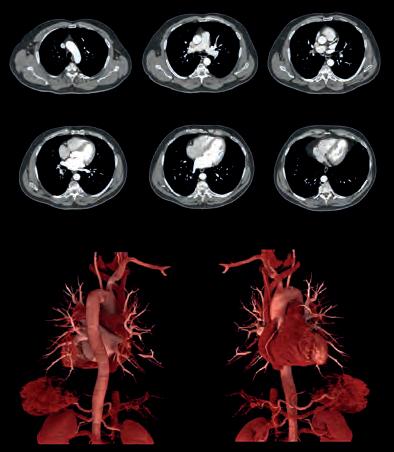

Knowledge of how the heart adapts to exercise and disease to be expanded by investment in research scholars and cardiac investigation techniques

Theaim of the Sports Cardiology & Research Partnership, a team of leading UK academics and medical institutions, is to advance the detection of serious cardiac disease. A new round of investment announced by Canon Medical Systems UK to appoint additional research scholars and expand echocardiography ultrasound and cardiac MRI investigation techniques will push its quest forward.

New studies are ongoing to quantitively assess the cardiac function during exercise of highly trained sports stars of the future. With Canon Medical UK’s support, the Sports Cardiology & Research Partnership has been able to generate one of the world’s largest datasets on the cardiovascular profile of young football players from the world’s leading football clubs and academies. Early data was presented to the 2021 International Olympic Committee World Conference on Prevention of Injury & Illness in Sport, while other research is currently under peer review with several leading journals.

Institute of Sport, Exercise and Health at UCL, where the programme is led by Profs. Guido Pieles and Mathew Wilson, the mobile lab is able to look into heart health using the latest medical imaging and analysis tools to identify pre-existing cardiac conditions that may predispose an athlete to sudden cardiac death.

The Sports Cardiology & Research Partnership is led by Professor Guido Pieles, the team cardiologist for Manchester United, Prof Graham Stuart, a Football Association expert consultant cardiologist, and Prof Craig Williams, director of CHERC. The research centres at Bristol, Exeter and ISEH London are using state of the art echocardiographic equipment by Canon Medical Systems. //